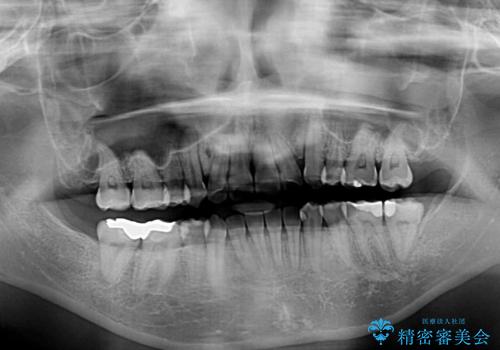

- 前歯の著しいデコボコを気にして来院された患者様です。

上顎の左右側切歯(前から2番目)が裏側に隠れいてる状態で、咬み合わせや清掃性に大きな問題が認められました。

左下に八重歯があったそうですが、当時は矯正治療を行うことを考えていなかったため、抜歯してしまったとのことでした。

叢生が著しいため、左下以外の第一小臼歯3本を抜去し、目立たないワイヤー装置にて矯正治療を行うこととしました。

これほど顕著に裏側に隠れいてる歯ですと、仕上がったときに両隣の歯と軸に差が認められることが多いのですが、殆ど違和感のない歯並びを達成することができました。